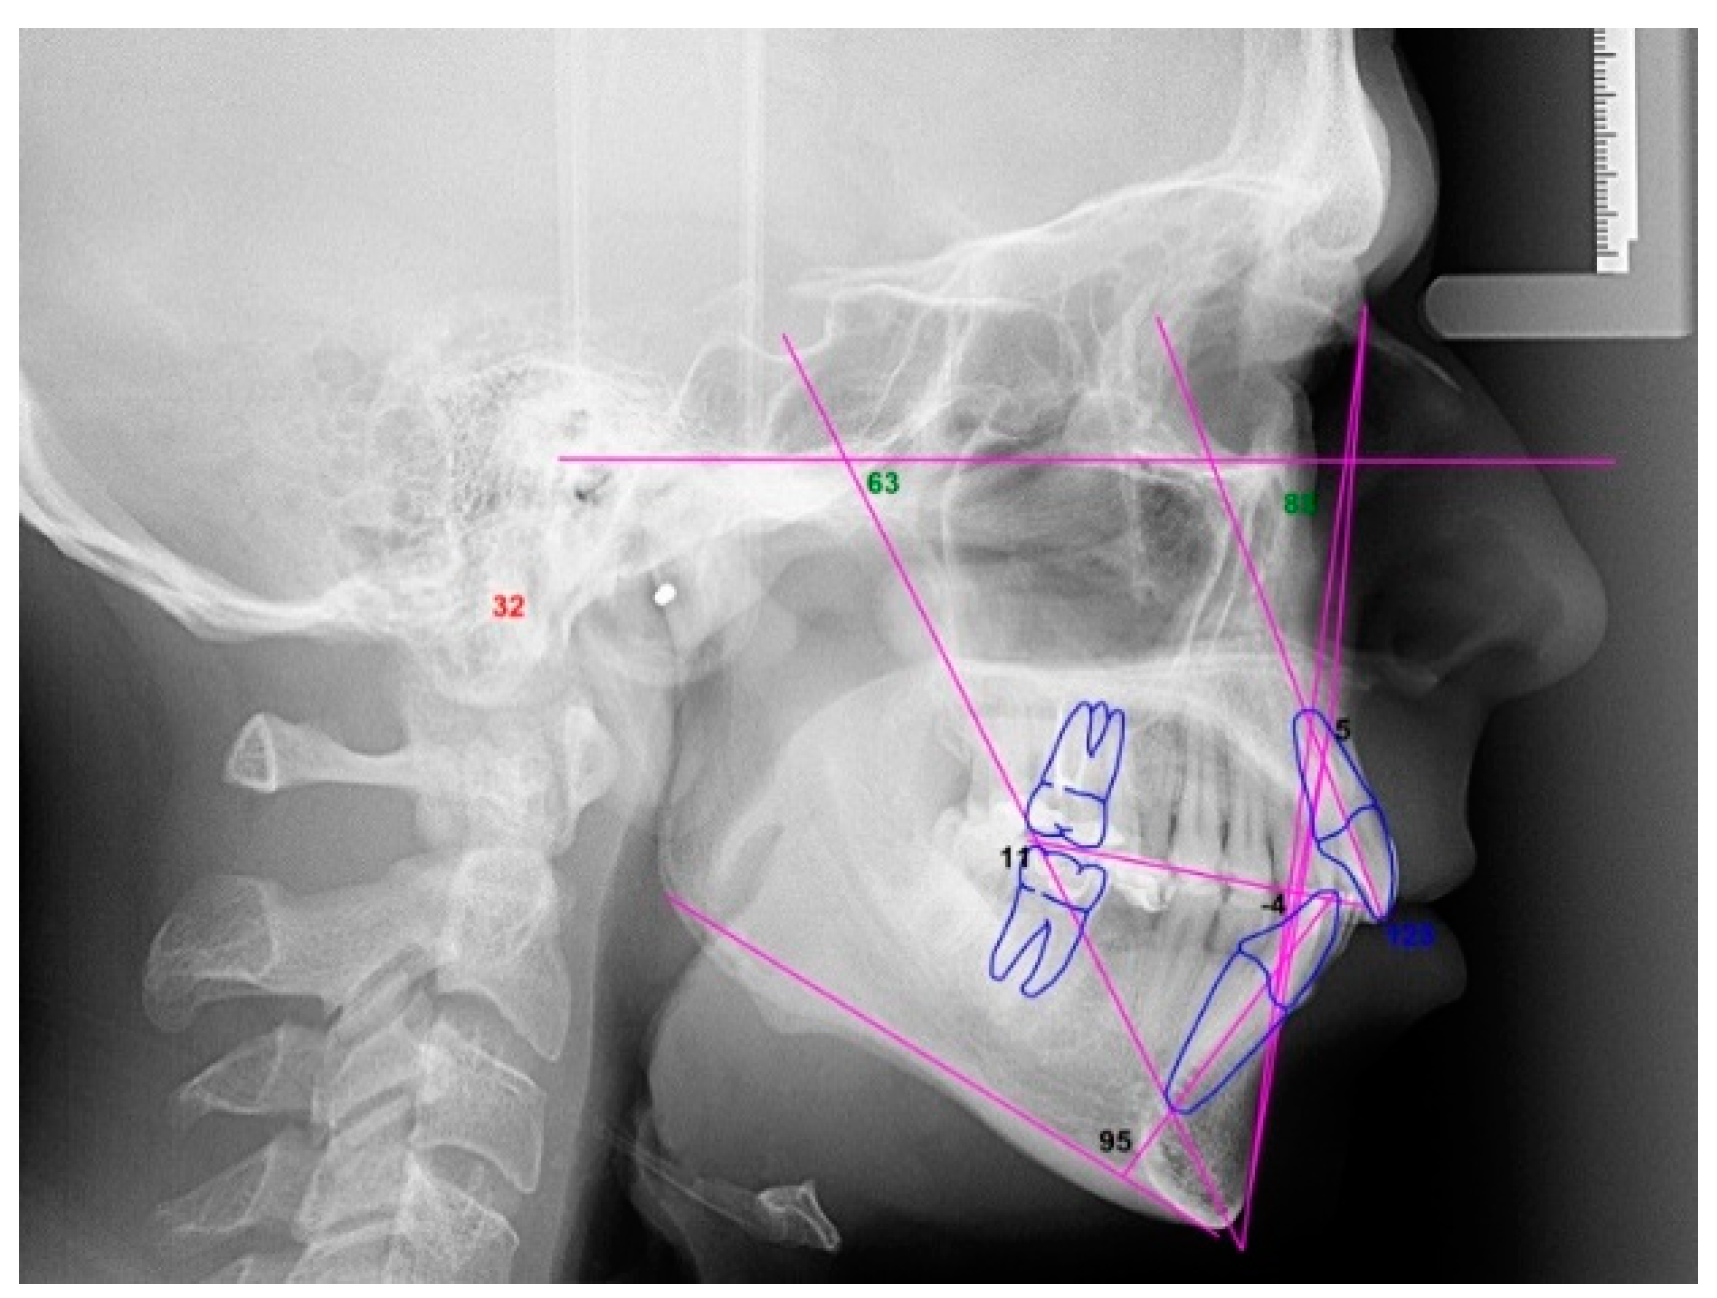

2.3.1. Example—Anterior Open-bite

2.3.2. Example 2—Extraction Space Closure